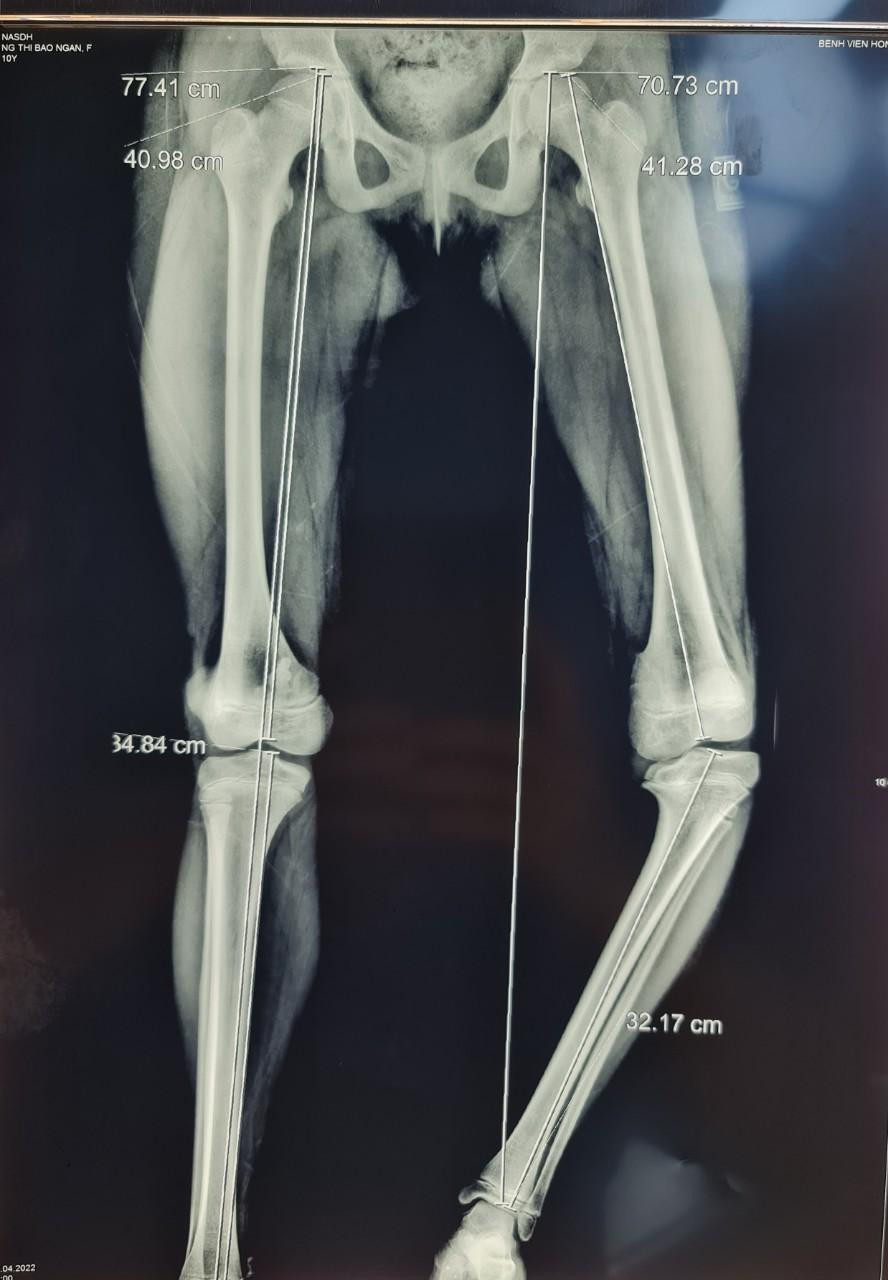

Ca thứ hai là bệnh nhi 13 tuổi, bị vòng kiềng từ nhỏ. Do không được điều trị nên tình trạng bệnh ngày càng nặng cộng thêm việc có chiều cao hạn chế (1m38) khiến dáng đi của bệnh nhi rất xấu. Điều này ảnh hưởng nhiều đến sinh hoạt và cuộc sống.

Theo BS. Đoàn, cả hai ca bệnh này đều phải can thiệp bằng phẫu thuật. Nếu không, khi lớn chân sẽ càng nặng hơn và làm biến dạng cả khớp gối, khớp cổ chân và khớp háng, sau này để lại di chứng, có thể dẫn tới việc không thể tự đi lại được, càng khó điều trị.

Phương pháp được BS. Đoàn áp dụng là cắt xương chỉnh trục và ghép xương, kết xương bằng nẹp khóa với các ưu điểm. Khi cắt xương chỉnh trục, làm ở vị trí ngay dưới mâm chày, không can thiệp vào khớp gối nên sau mổ cơ bàn chỉnh được hết biến dạng.

BS. Đoàn cho biết, khi cắt xương chỉnh trục và ghép xương vào chỗ khuyết xương thì làm tăng chiều cao của xương lên từ 1,5 - 2,5cm. Kết xương bằng nẹp khóa vững chắc nên không phải bó bột, sau 2 tuần cắt chỉ là tập phục hồi chức năng, sau 3 tuần tập đi được bằng nạng, sau 6 tuần đã đi lại bình thường.

Theo BS. Đoàn, nguyên tắc cơ bản là phải cắt xương, chỉnh lại trục chân, kết hợp xương sao cho đủ vững. Đối với trẻ đang phát triển cần hết sức chú ý về kỹ thuật, sao không để gây tổn thương sụn phát triển ở các đầu xương. Phải cân nhắc thời điểm nào là phẫu thuật cho phù hợp với mức độ biến dạng cũng như tuổi của bệnh nhi.